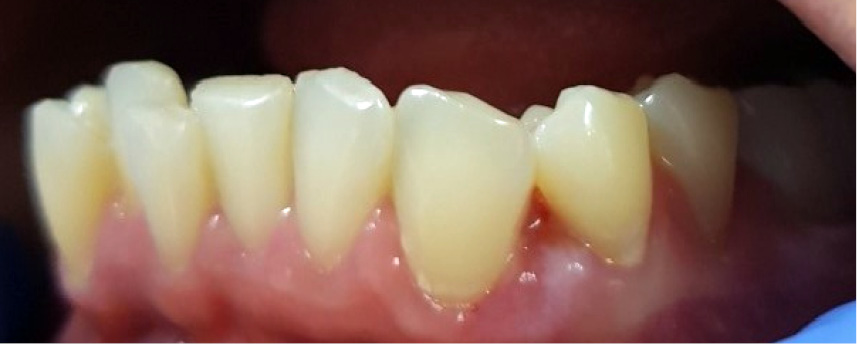

STRESZCZENIE: Nadziąślaki stanowią różnorodną grupę zmian rozrostowo-guzopodobnych o wieloczynnikowej etiologii. Wywodzą się z mezenchymy tkanek przyzębia – z dziąseł, ozębnej oraz okostnej. Według aktualnie obowiązującej Klasyfikacji Chorób Przyzębia z 2017 r. nadziąślaki zaliczają się do procesów odczynowych i należą do chorób dziąseł niewywołanych płytką. Wyróżnia się nadziąślaki włókniste, fibroblastyczne nadziąślaki wapniejące, nadziąślaki ropotwórcze oraz ziarniniaki olbrzymiokomórkowe. Istnieją różnorodne metody leczenia nadziąślaków: usunięcie zmiany za pomocą skalpela, lasera diodowego, CO2 lub Er:YAG, noża elektrochirurgicznego, krioterapii lub sklerotyzacji. Należy jednak pamiętać, że każdą zmianę należy przekazać do badania histopatologicznego.

SUMMARY: Epulides are a diverse group of tumour-like hyperplasia lesions of a multifactorial aetiology. They originate from the mesenchyme of the periodontal tissues – the gums, periodontium and periosteum. According to the current Classification of Periodontal Diseases (2017) epulides are reactive processes and belong to gingival diseases not caused by plaque. There are fibrous epulides, fibroblastic calcified epulides, pyogenic epulides and giant cell granulomas. There are various methods of treating epulides: removal [...]